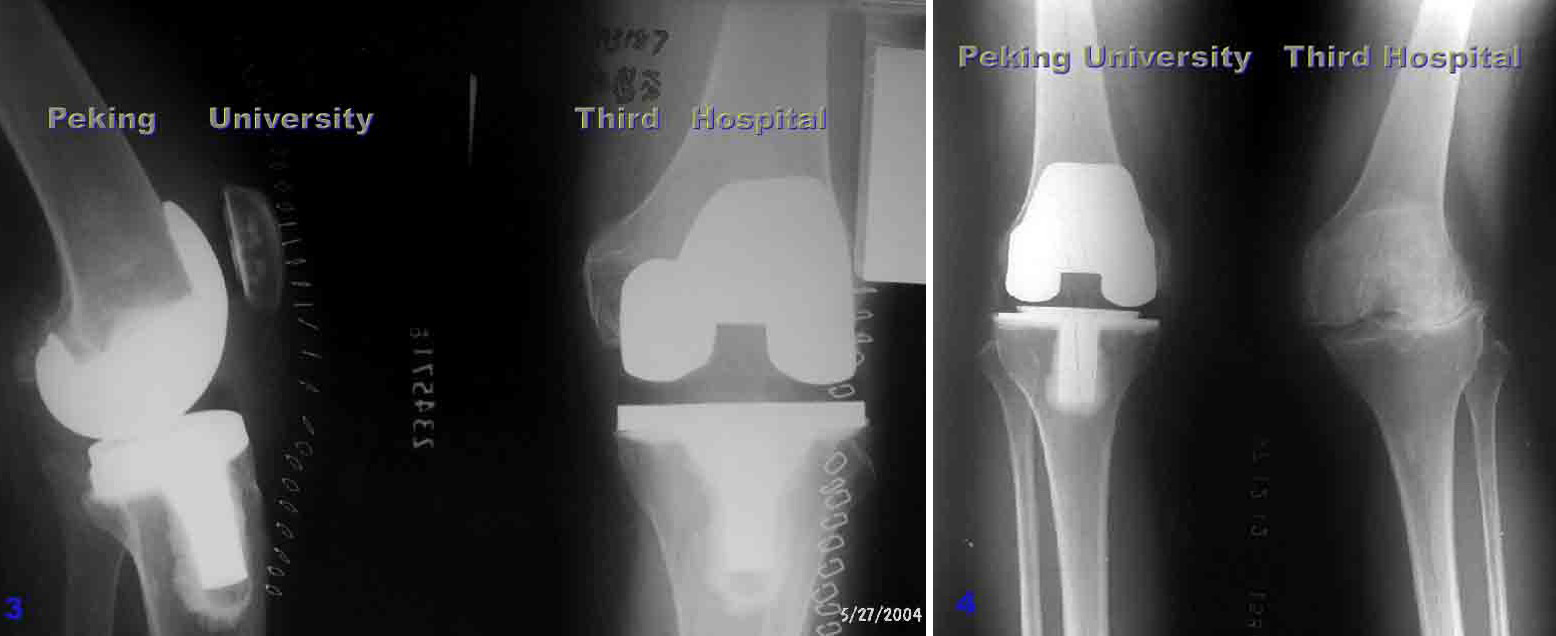

单髁膝关节置换术后8年,塌陷,接受全膝关节表面置换术

单髁置换

膝关节内侧间隙狭窄,适合单髁置换,手术后恢复快,

关节活动最大限度保留